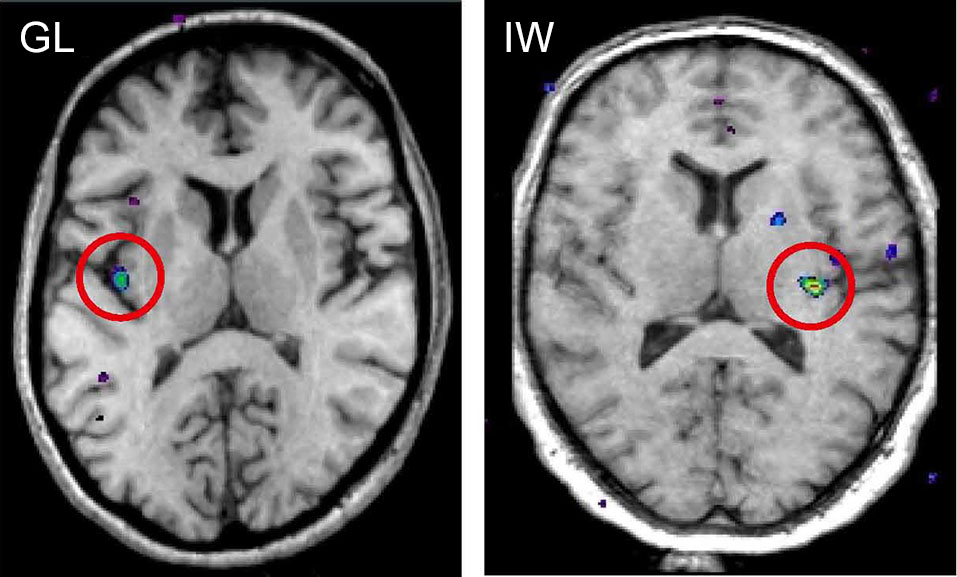

When functional magnetic resonance imaging (fMRI) is used to study brain responses to touch stimuli in neurologically intact subjects and in neuronopathy subjects lacking Aβ afferents, different sensory areas are activated by Aβ and CT afferents. In healthy subjects soft brush stroking activates the classical somatosensory areas S1 and S2 as well as insular cortex, notably the posterior part of the contralateral insular cortex (Olausson et al., 2002). When similar brushing stimuli are applied to the neuronopathy subjects lacking Aβ afferents (GL and IW) only the posterior insular region is activated (Olausson et al., 2002, 2008; Figure 4). Further, there is a somatotopic organization of CT responses in the posterior insular cortex with forearm projecting anterior to thigh stimulation (Bjornsdotter et al., 2009). The somatotopic arrangement suggests that CT afferents follow the thin-fiber spinothalamic pathway with the posterior insular cortex as the primary cortical receiving area (Craig, 2002). No corresponding insular activation was found for brush stroking in the C-fiber denervated HSAN-V subjects (Morrison et al., 2011).

Figure 4. fMRI activation in posterior insular cortex evoked by selective stimulation of CT afferents in the neuronopathy subjects GL and IW lacking Aβ afferents. In both subjects, the posterior insular activation was contralateral to the stimulated forearm and reflects differences in blood oxygen level dependent (BOLD) signal during soft brush stroking and a baseline condition of rest (Olausson et al., 2002; Olausson et al., 2008).